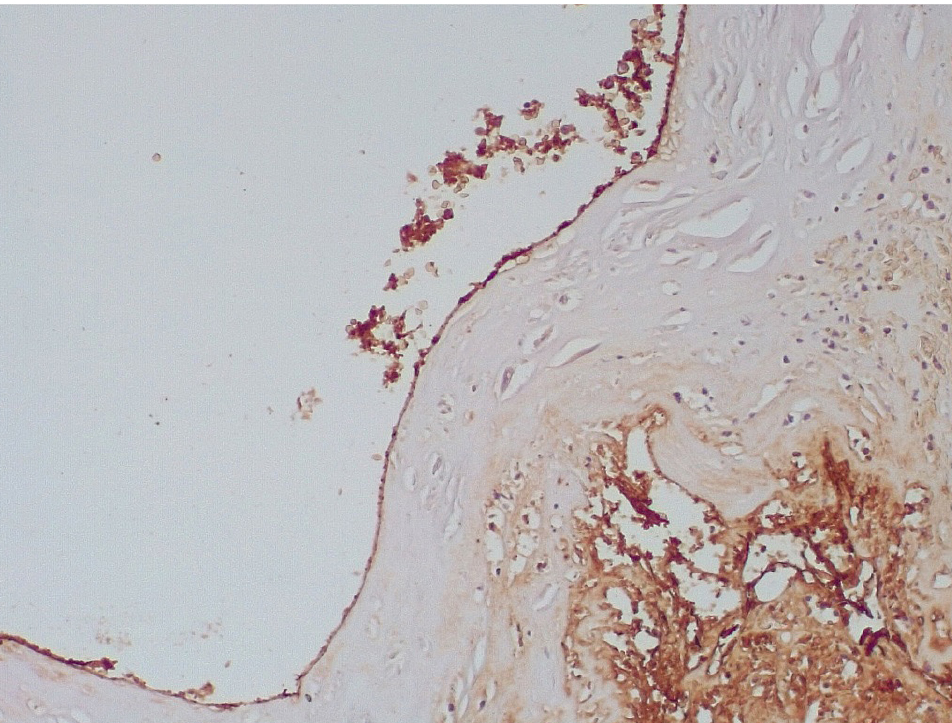

Обращало внимание, что в местах «оголенного» эндотелия КА отмечалась слабая экспрессия белка CD31, что указывало на выраженные дистрофические и некробиотические изменения клеток (рис. 2). При этом экспрессия ФВ была яркой, выраженной на всем протяжении интимы КА (рис. 3).

Сохранялась резковыраженная яркая экспрессия ФВ как со стороны интимы, так и субинтимально, в участках альтерации атером (рис. 8). В то же время экспрессия белка CD31 была негативной на всем протяжении стенок КА.

Наиболее значимым маркером эндотелиальной дисфункции, отражающим нарушение коагуляционных свойств крови, является белок фактор Виллебранда, экспрессия которого была резко выраженной во всех группах умерших после стентирования КА.

Показано, что после стентирования в течение первых 3 суток в стенках КА вокруг атером встречаются геморрагии, мелкие лейкоцитарные инфильтраты, повреждение клеток эндотелия, что наряду с экспрессией фактора Виллебранда является предиктором для формирования пристеночных тромбов.

Позднее, спустя 3–7 суток, возникают пристеночные смешанные тромбы, которые через 7–15 суток имеют признаки организации, что сопровождается резкой яркой экспрессией белка фактора Виллебранда.